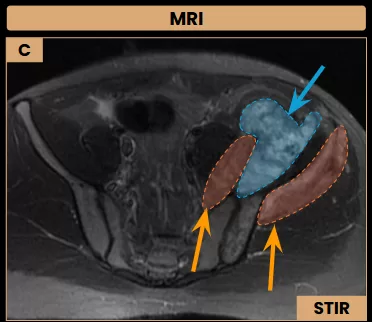

Image C: Axial MRI shows a necrotic area (arrow – blue) within the soft tissue component of the lesion, which also infiltrates the iliopsoas and gluteus minimus muscles (arrows – orange).